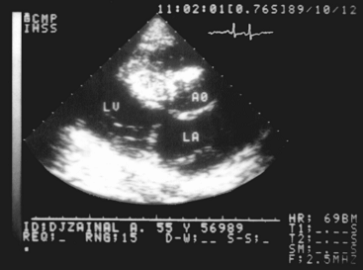

Рис. 11а). Двухмерная эхокардиограмма больного с обструктивной гипертрофической кардиомиопатией (на эхокардиограммах в М-режиме полости сердца - светлые поля, плотные структуры - темные): а - резко утолщенная межжелудочковая перегородка (VS) суживает выходной тракт левого желудочка LV - субаортальный стеноз; видны просветы аорты (АО) и левого предсердия (LA).